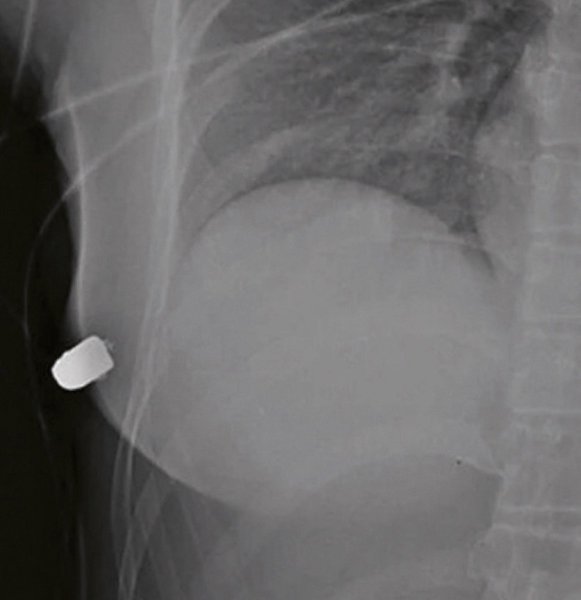

Врачи клиники в городе Миссиссога обнаружили, что в правом силиконовом имплантате девушки находится инородное тело. После рентгена выяснилось, что у неё сломанное ребро, а томография показала незначительные повреждения тканей лёгких.

Медики отметили, что силиконовый имплантат сыграл роль защитного барьера, предотвратив более серьёзные травмы.